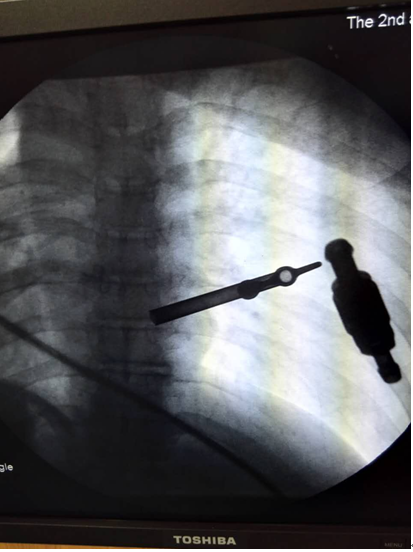

术前定位1

(术前定位1

术前定位2

(术前定位2